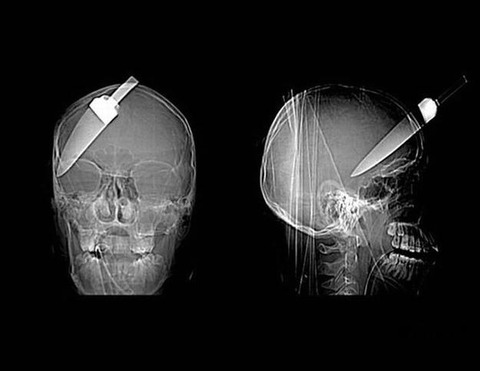

ちなみに怪我の理由は目に棒が刺さった

さらに蹲ってるところを棒で殴り口も切れ、

頭に痣まで作ったらしい

怖い事を言うようで申し訳ないが、頭に痣が出来る程危害を加えられている場合、下手すると脳溢血だかなんだかを発祥してしまう可能性もある。

良くニュースなどで虐待されて亡くなってる子供とか、脳に血が溜まってとか聞く。

お金がかかるけど、弟さんは一度精密検査の受診をお勧めする。